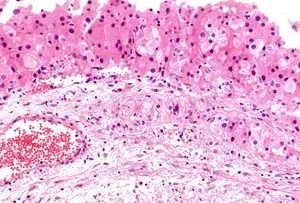

- Korpuş Luteum Kisti: Yumurtlama sonrası olgunlaşan folikül, döllenme gerçekleşmezse korpus luteum adı verilen yapıyı oluşturur. Korpus luteum bazen sıvı birikmesiyle kist halini alabilir. Bu kistler genellikle zararsızdır ancak bazen ağrıya yol açabilir.